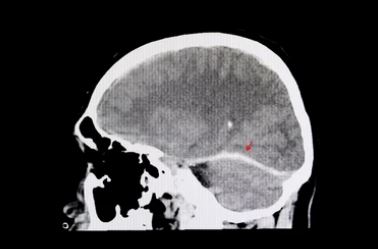

Effect of Transcranial Low-Level Light Therapy vs Sham Therapy Among Patients With Moderate Traumatic Brain Injury A Randomized Clinical Trial Maria Gabriela Figueiro Longo, MD, MSc1; Can Ozan Tan, PhD1,2; Suk-tak Chan, PhD1,3; et alJonathan Welt, BS4; Arman Avesta, MD5; Eva Ratai, PhD1; Nathaniel David Mercaldo, PhD1; Anastasia Yendiki, PhD3; Jacqueline Namati, PhD1; Isabel Chico-Calero, PhD1; Blair A. Parry, BA1; Lynn Drake, MD1; Rox Anderson, MD1; Terry Rauch, PhD6; Ramon Diaz-Arrastia, MD, PhD7; Michael Lev, MD1; Jarone Lee, MD1; Michael Hamblin, PhD1; Benjamin Vakoc, PhD1; Rajiv Gupta, MD, PhD1 Author Affiliations Article Information